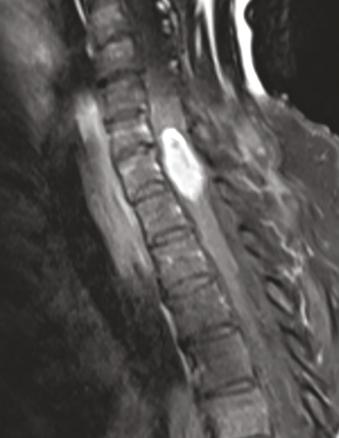

Une femme de 70 ans, tabagique sevrée à 45 paquets-années, présente un syndrome médullaire d’évolution rapide (3 semaines). L’imagerie par résonance magnétique montre une masse fusiforme intramédullaire au niveau de C7 (fig. 1 ). Le bilan lésionnel met en évidence un nodule pulmonaire évocateur de lésion néoplasique primitive (fig. 2 ), et plusieurs autres lésions secondaires : cérébrale, ganglionnaires et hépatiques. La biopsie hépatique confirme le diagnostic de carcinome pulmonaire (marqueur TTF-1 positif) métastatique peu différencié. L’évolution rapidement progressive a conduit à la mise en place de soins palliatifs exclusifs.

Les métastases intramédullaires sont rares. Les cancers pulmonaires et du sein en sont les principaux pourvoyeurs.2, 3 Elles constituent la première manifestation du cancer dans 10 à 25 % des cas.2, 4 L’évolution rapide de l’atteinte neurologique est en faveur du diagnostic de métastase intramédullaire.2 Le pronostic est sombre, avec une médiane de survie de trois à quatre mois.2,3,4 Devant la rareté des métastases intramédullaires, le traitement n’est pas encore codifié et dépend de la nature du cancer primitif. La résection chirurgicale peut être réalisée sur les lésions isolées.4 La radiothérapie constitue une alternative thérapeutique.3 Ces deux options ont un effet modéré sur la survie des patients.